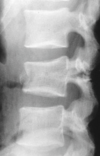

What is seen on imaging?

- Xray

- intraspinal distance increases

- pedicles widening- AP

- kyphosis

- Retropulsion

- >50% loss in height